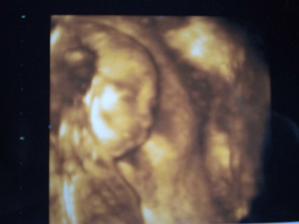

11.10. mi Jáchyma prohlížela paní Dr. zaskakující za toho mého. Ukázala mi ledviny, žaludek, plný močák i pracující srdíčko 😉 Taky zkontrolovala rtíky, které měl Jáchym hezky našpulené a žádný rozštěp tam není 😉 Jen nemáme fotečku, páč paní Dr. neumí s 3D UTZ.

Jáchym má cca 1700g, takže prý tak akorát 😉